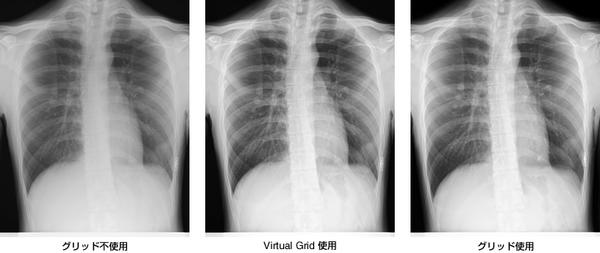

〜DR方式の「CALNEO Cシリーズ」でX線撮影時の画質および作業性を向上 / 病室や救急での撮影で,グリッドを使わずに高コントラスト画像を実現〜

今回提供する「Virtual Grid」は,X線とデジタル画像に対する解析技術を組み合わせることで,散乱線成分を高速かつ忠実に再現する独自の「散乱線推定技術」を用いている。この技術により,撮影画像から推定された散乱線成分を,元の撮影画像から除去することで,散乱線により低下した画像のコントラストを高めることができる。さらに,「Virtual Grid」はグリッドの種類を変えた場合と同じように,画像のコントラストを調整することができ,また複数枚のグリッドの持ち運びや入れ替えが不要なので,作業性の向上を実現する。

撮影条件(X線の強さ,量など)や撮影部位,被験者の体格などさまざまな要因の影響を受ける散乱線成分を高速かつ忠実に再現する「散乱線推定技術」を開発。画像ごとにコントラストを自動で調整している。

撮影画像から推定された散乱線成分を,元の撮影画像から除去することで,散乱線により低下した画像のコントラストを高めることができる。